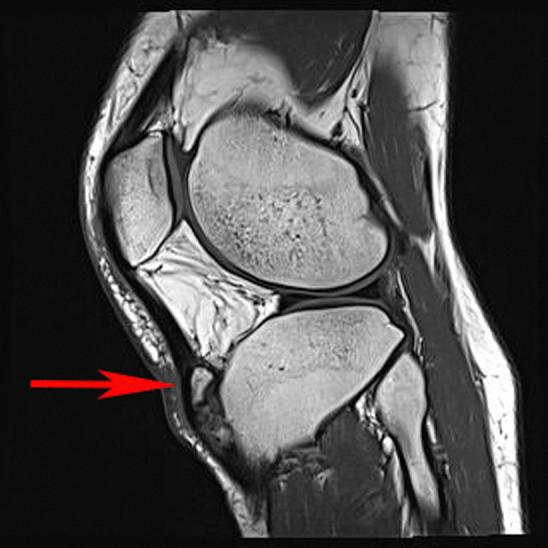

Arthroscopic resection of symptomatic unfused tibial tubercle ossicles causing chronic anterior knee pain due to recalcitrant Osgood-Schlatter disease has been shown to be a reproducible arthroscopic technique. Although a number of other surgical techniques have been described, including ossicle excision and tubercle-plasty, drilling of the tibial tubercle, bone peg insertion to induce fusion, open excision of loose fragments, direct bursoscopic ossicle resection, and closing-wedge tubercle osteotomy, with varied outcomes, this technique offers a minimally invasive approach with low risk. Complications including injury to the patellar tendon and scarring of the anterior fat pad have been previously reported, but this approach can be performed with minimal fat pad debridement and direct visualization of the patellar tendon during all resections. This article presents a technique for arthroscopic resection and debridement of unfused ossicles in patients with chronic anterior knee pain due to Osgood-Schlatter disease by use of minimally invasive arthroscopic techniques that are used in standard knee arthroscopy and should be familiar to most arthroscopists.

对于因难治性胫骨结节骨软骨炎导致慢性前膝痛的有症状未融合胫骨结节小骨,关节镜下切除已被证明是一种可重复的关节镜技术。尽管已经描述了许多其他手术技术,包括小骨切除和结节成形术、胫骨结节钻孔、插入骨栓诱导融合、开放切除游离碎片、直接关节镜下小骨切除以及闭合楔形结节截骨术,且结果各异,但该技术提供了一种微创方法,风险较低。先前已报道过包括髌腱损伤和前脂肪垫瘢痕形成等并发症,但这种方法在所有切除过程中可通过最小限度的脂肪垫清创和直接观察髌腱来实施。本文介绍了一种通过使用标准膝关节镜检查中使用的微创关节镜技术,对因胫骨结节骨软骨炎导致慢性前膝痛的患者进行关节镜下未融合小骨切除和清创的技术,大多数关节镜医生应该熟悉这些技术。